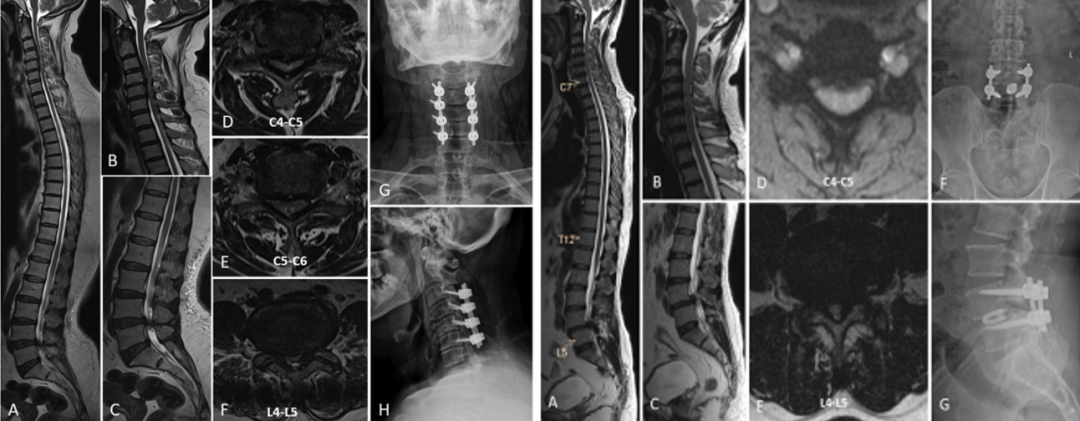

B型:颈腰椎型,CT-TSS,分为4个亚型

B1型-同时有上肢和下肢脊髓症状病。

B2型-以下肢脊髓病为主,无手部脊髓病症状。

B1型有3例(50%)需接受二阶段减压,首先进行颈椎减压,然后按计划进行胸椎减压,平均间隔为4.5个月。术前平均Nurick分级从4.6±0.5改善至1.8±0.3;B2型只有1名(20%)患者因持续的脊髓症状需要另行颈椎手术。